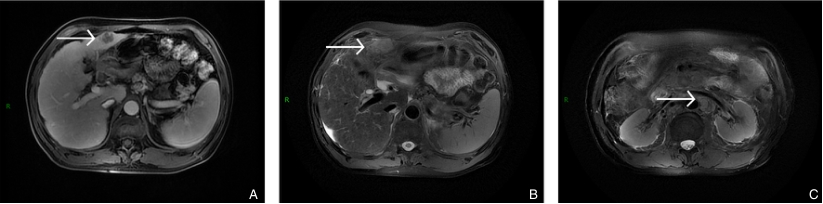

图6 2023年6月2024年9月与患者术后复查MRI A:复查可见复发淋巴结;B-C:复查病变在T1加权成像(T1WI)中呈稍低信号,在T2加权成像(T2WI)中呈高信号Fig.6

图6 2023年6月与2024年9月患者术后复查MRI A:复查可见复发淋巴结;B-C:复查病变在T1加权成像(T1WI)中呈稍低信号,在T2加权成像(T2WI)中呈高信号Fig.6